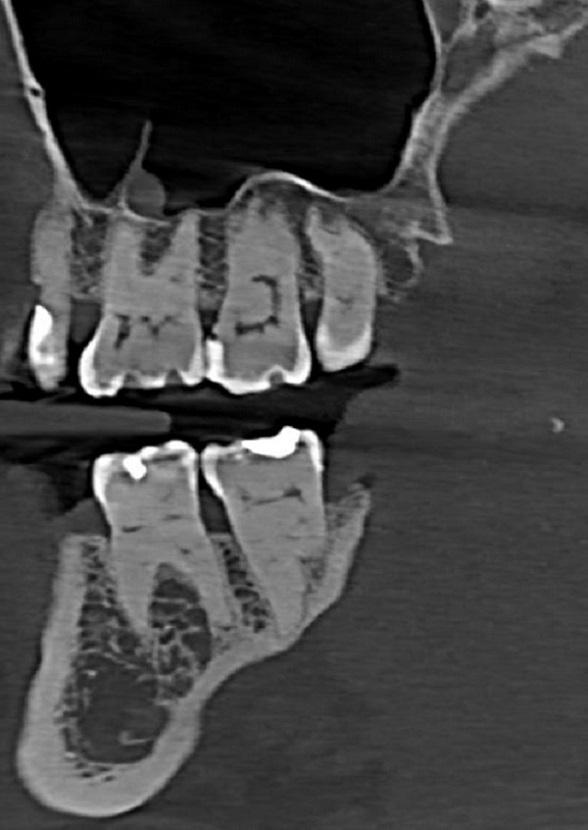

CBCT szczęki i żuchwy.

Zęby przedtrzonowe i trzonowe z cechami taurodontyzmu.

Wydłużone komory zębów o prostokątnym kształcie i skrócone korzenie na skutek przesunięcia furkacji w kierunku wierzchołkowym.

Częściowo zobliterowane światło komór oraz kanałów korzeniowych.

Zmiany zapalne wokół wierzchołków korzeni zębów 31,41.

Ząb 41 – leczony endodontycznie.

Skomplikowany system kanałowy zęba ,dwa podstawowe ,kanały poprzeczne . Materiał endodontyczny widoczny w kanale wargowym oraz częściowo zapłynął do kanalików poprzecznych.

Puste światło kanału językowego.

Ząb 31 o podobnej do zęba 41 anatomii wewnętrznej.